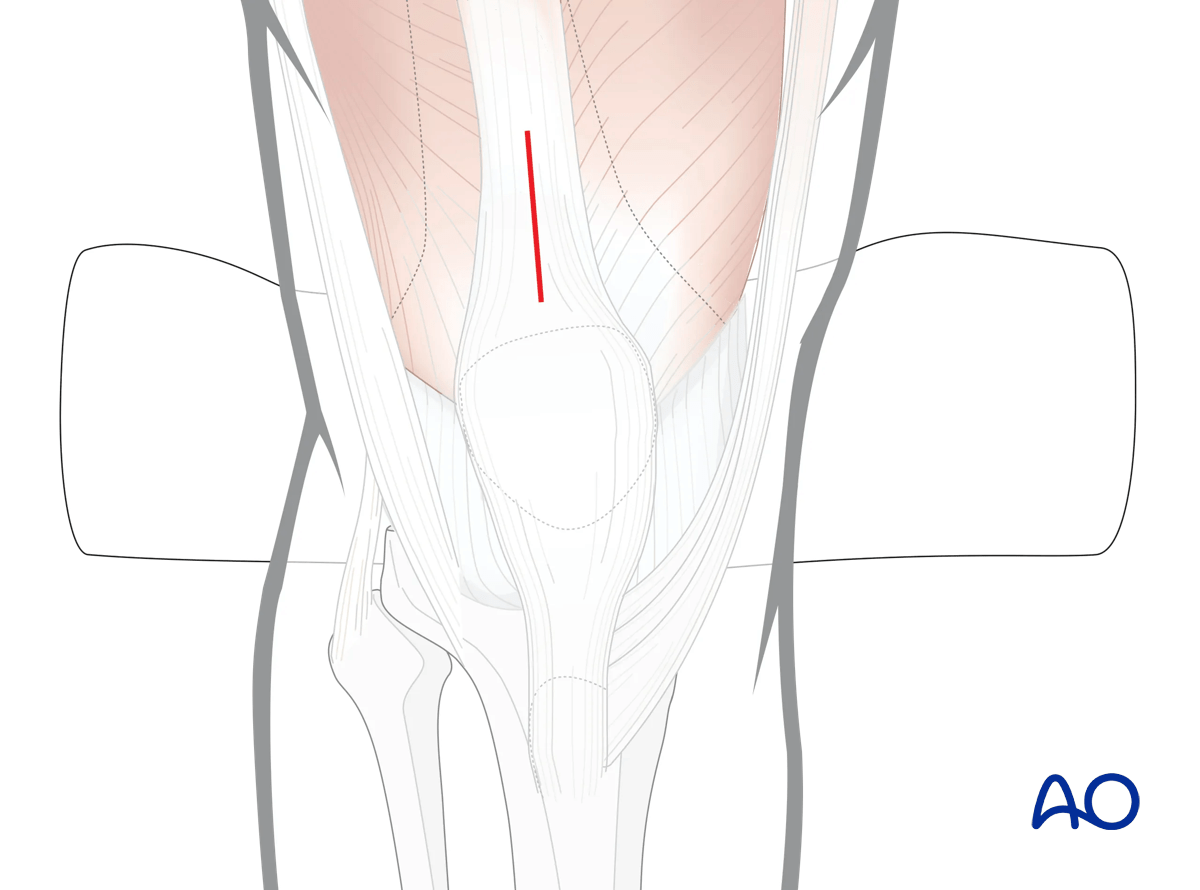

Incision

Locate the fracture by palpation or with fluoroscopy. Make a small longitudinal incision over the fracture. Avoid making an incision of the anteromedial surface of the tibia as wound healing can be impaired. Extend the incision sufficiently for access. Free up one side of the fracture at a time, with minimal dissection.

Suprapatellar intramedullary nailing, open reduction, incision